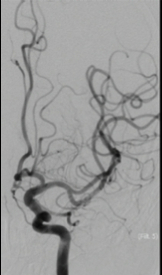

CT scanner angiography of brain revealed that there was no imagine of Left ICA as well as no hemorrhage. The patient was asumpted to have acute cerebral infarction in a situation of peri- endarterectomy surgery, that meaned this was an unknown onset stroke

The DSA imagine showed a totally occlusion from the Left CCA. Assumpting that this must be a dissection lesion, carotid stenting was perform with 2 Carotid stent 8x40mm from CCA up to ICA after a loading dose of DAPT. After procedure, the patient was recovery at mRS of 1.